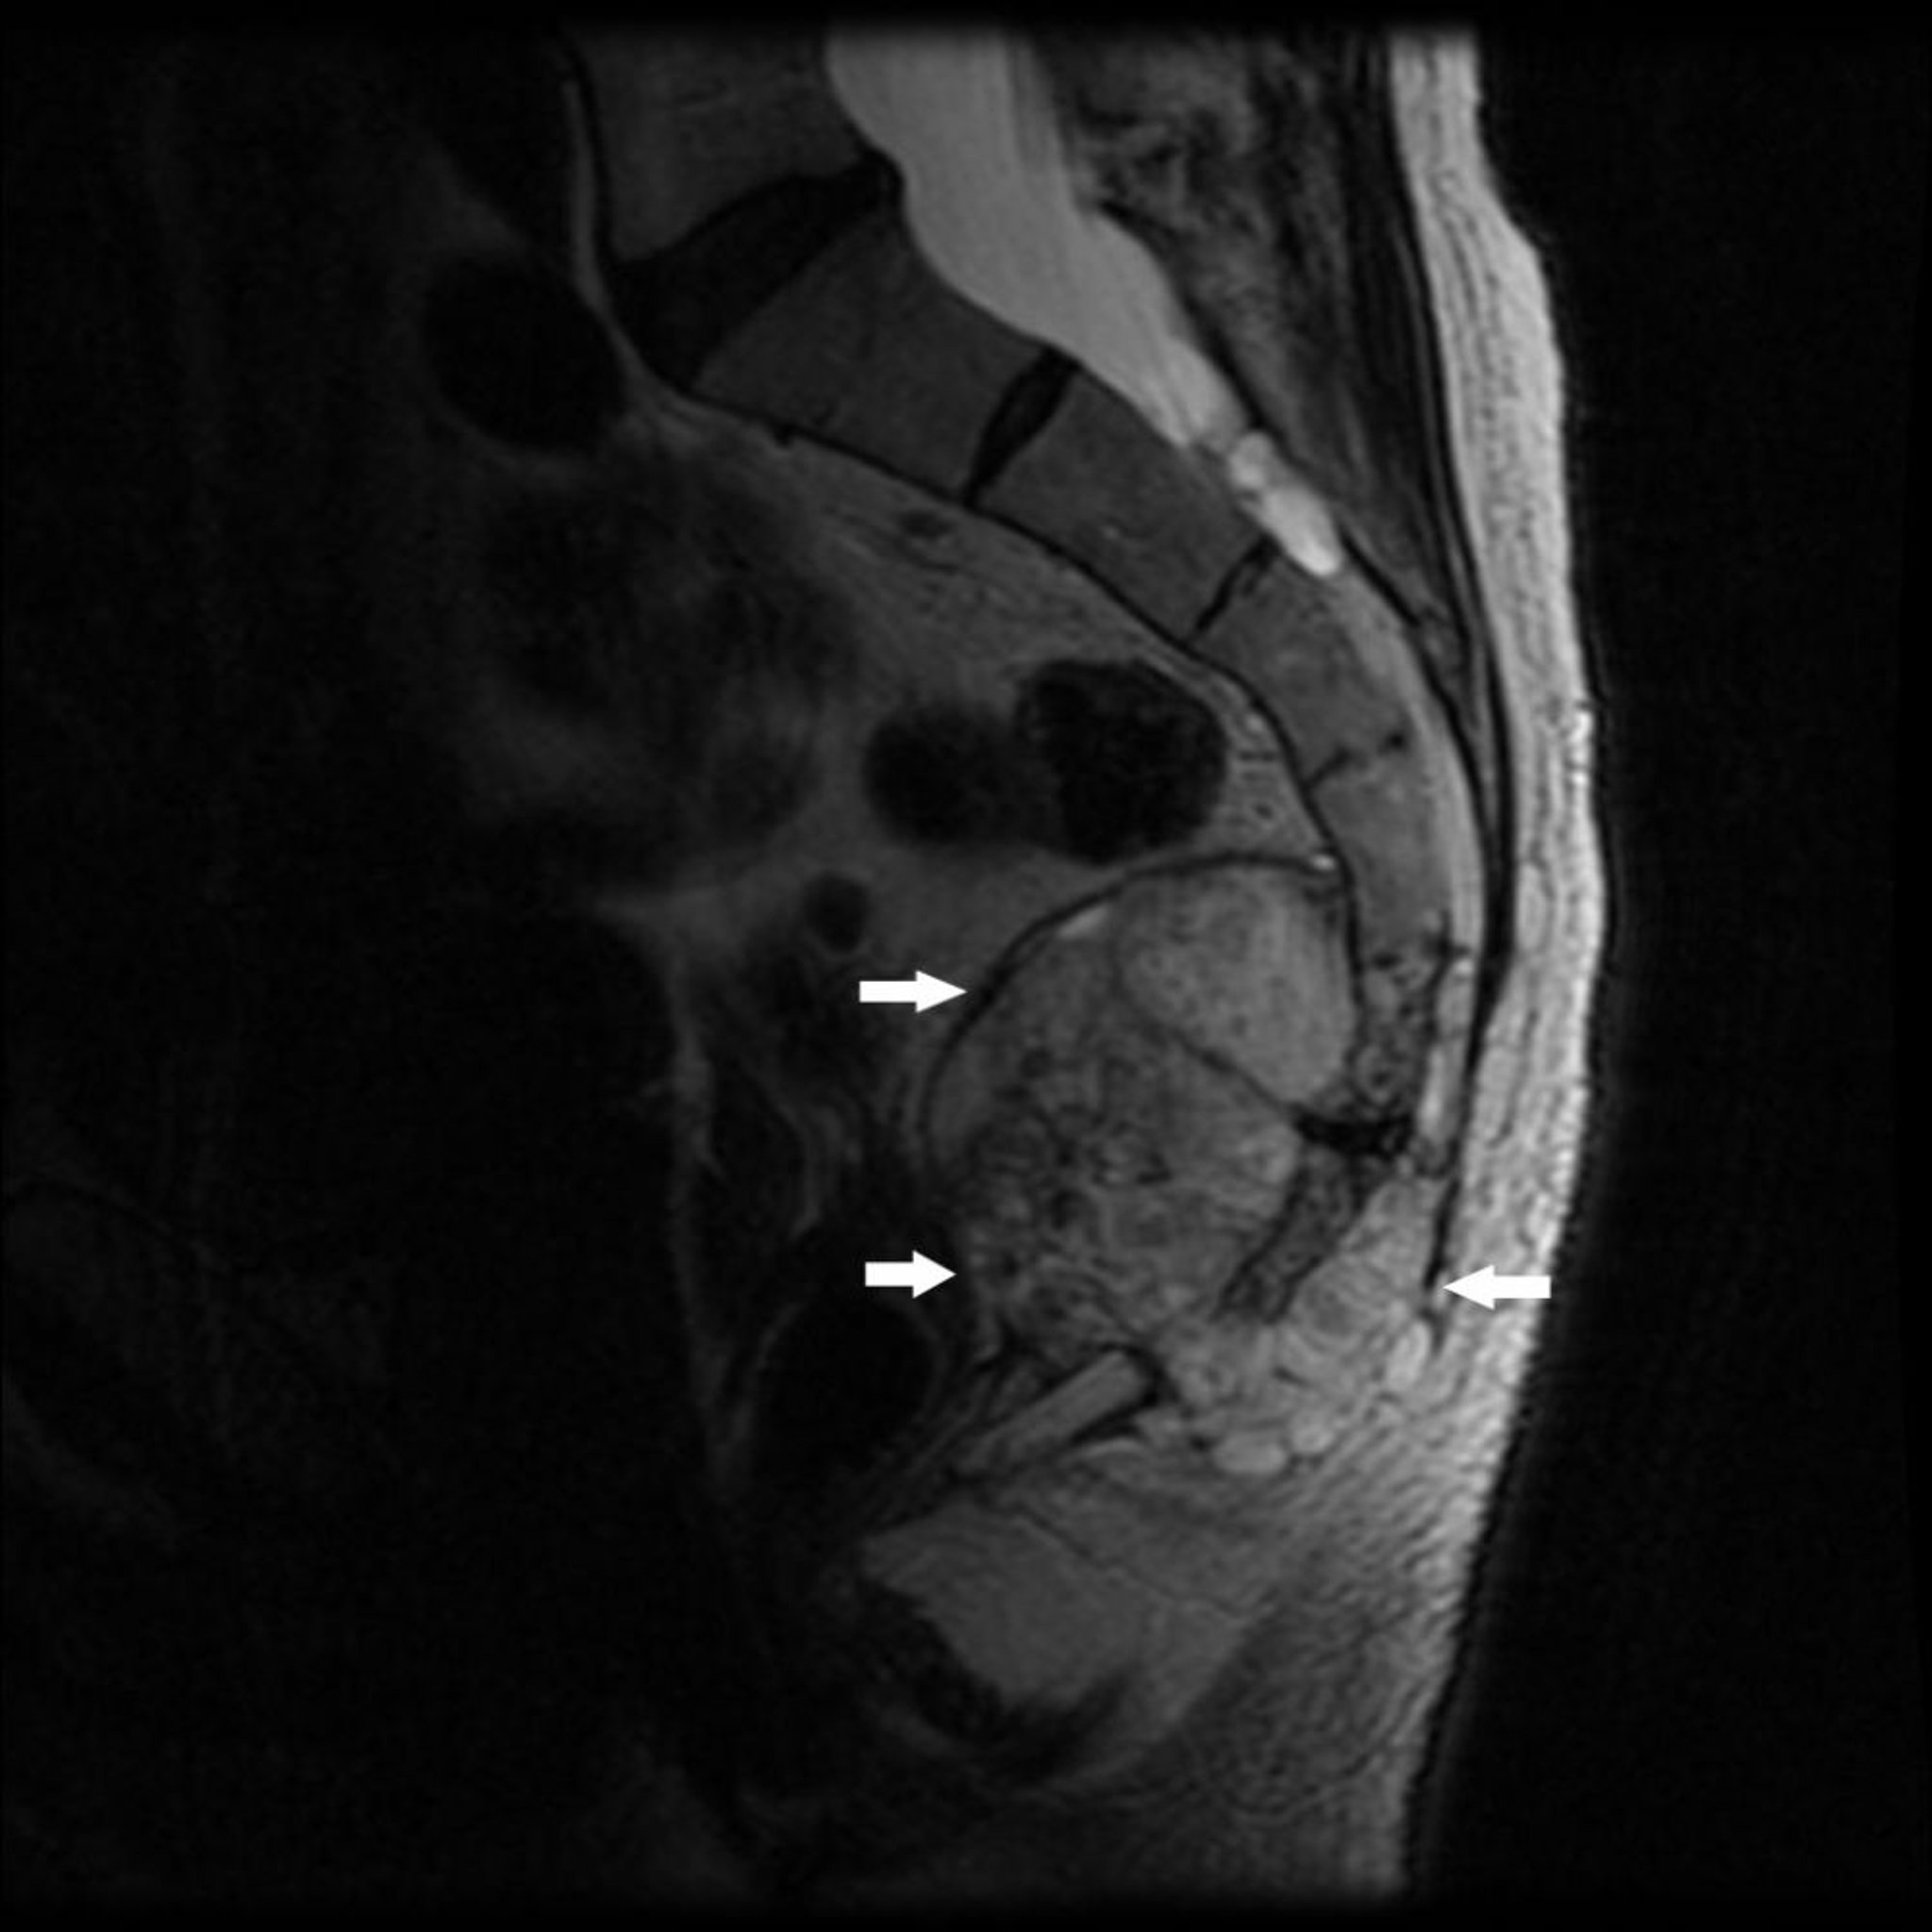

脊索腫

このMRI像では,脊椎末端および尾骨の付近に骨破壊および軟部組織腫瘤(矢印)を伴う腫瘍が認められ,これは脊索腫に典型的な所見である。

Image courtesy of Michael J.Joyce, MD, and Hakan Ilaslan, MD.